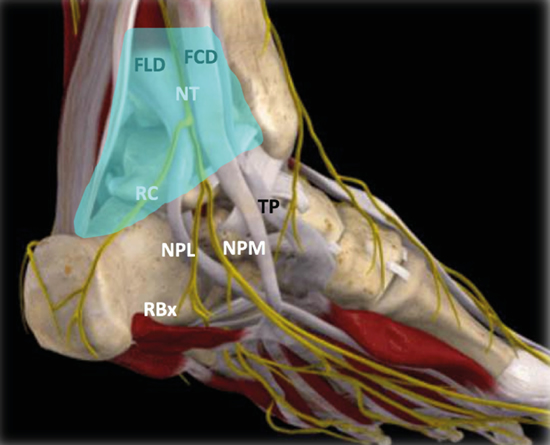

El nervio tibial, en su tránsito por la cara medial del tobillo y del pie, dará las ramas calcáneas mediales, el nervio plantar medial, el nervio plantar lateral y la primera rama del nervio plantar lateral o rama de Baxter3. El nervio peroneo profundo se localiza en profundidad a la musculatura extensora del primer radio a la altura del tobillo. El nervio peroneo superficial discurre por el borde anterior del peroné para llegar escindido al tobillo en los nervios cutáneo dorsal medial y cutáneo dorsal intermedio. El nervio sural, situado en el aspecto posteromedial de la pierna adyacente a la vena safena menor, dará las ramas calcáneas laterales antes de girar retromaleolar al peroné hacia el pie para denominarse como el nervio cutáneo dorsal lateral (Figuras 2 y 3)2,3.

Figura 3. Túnel tibiotalocalcáneo. El nervio tibial (NT) se divide en la rama calcánea (RC), el nervio plantar medial (NPM) y el nervio plantar lateral (NPL) del que se escinde la rama de Baxter (RBx). Las estructuras musculotendinosas tibial posterior (TP), flexor largo del primer dedo (FLD) y flexor largo de los dedos (FCD) acompañan al nervio tibial en su recorrido por la cara medial del tobillo y el pie. Imagen modificada de la App Ankle & Foot Pro III.

Figura 5. Túnel tibiotalocalcáneo. La porción proximal o túnel tibiotalar superior en azul. Estructuras nerviosas: nervio tibial (NT), rama calcánea (RC), nervio plantar lateral (NPL), nervio plantar medial (NPM), rama de Baxter (RBx). Estructuras musculotendinosas: tibial posterior (TP), flexor largo del primer dedo (FLD) y flexor largo de los dedos (FCD). Imagen modificada de la App Ankle & Foot Pro III.